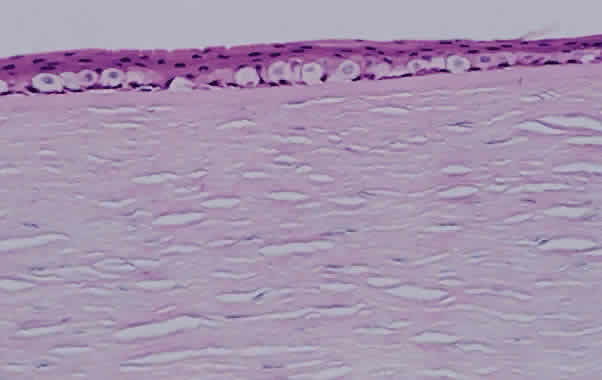

PROGRESSIVE OUTER RETINAL NECROSIS. Descriptively named, progressive outer retinal necrosis is a progressive, multifocal, necrotizing inflammation of the outer retina. Unlike CMV retinitis, it is not associated with significant retinal vasculitis. Caused by the varicella zoster virus, it often follows an episode of cutaneous zoster.108 Rutzen and associates109 reported the histopathology from two cases of progressive outer retinal necrosis requiring retinal biopsy. Retinal necrosis was present in one, with the other showing only retinal atrophy (Fig. 12). Both revealed herpes group viral DNA. Unlike the typical occlusive vasculitis seen in CMV retinitis, retinal vessels were patent in the case with retinal necrosis.

Fig. 12. Photomicrograph of retina from a patient with progressive outer retinal necrosis showing loss of normal retina architecture but preservation of retinal vessels (arrow) (hematoxylin and eosin; × 200).